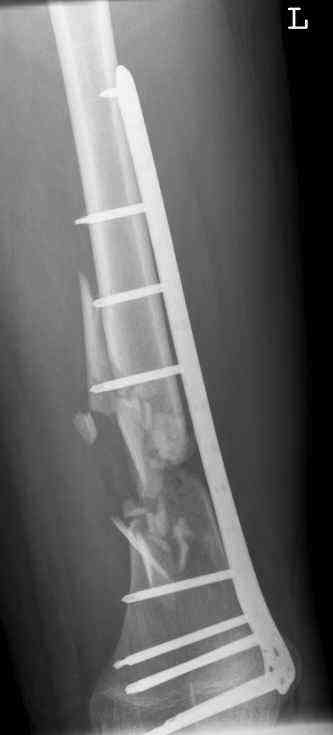

july 05: LISS femur, LCP plate tibia, double recon. plate post. acetabulum

aug 06: blade plate + bone graft

nov 06: revision blade plate

feb 07: retrograde nail + bone graft + BMP